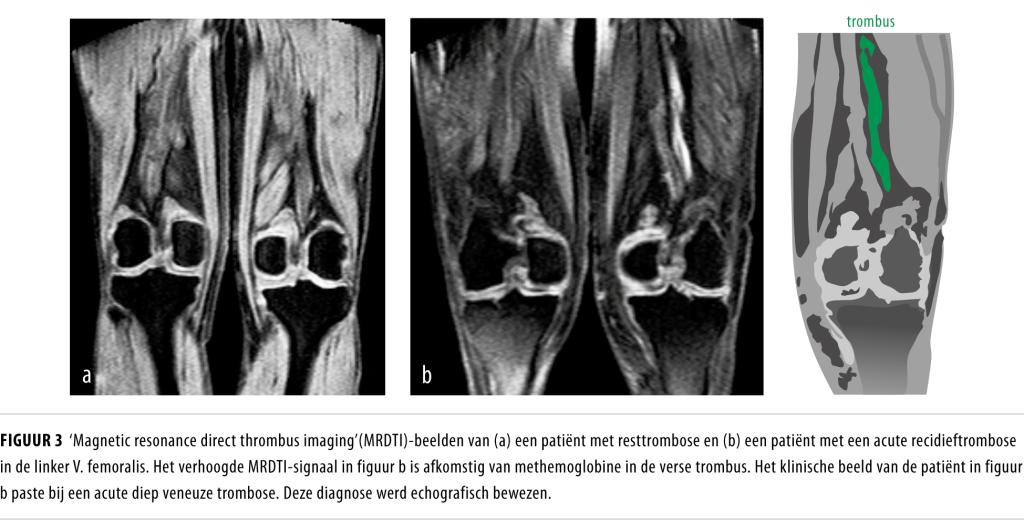

• Een recidief-DVT in het ipsilaterale been is echografisch niet goed vast te stellen, vooral niet als er geen uitgangsechografie is verricht na het staken van de antistollingsbehandeling voor de eerste veneuze trombo-embolische episode.